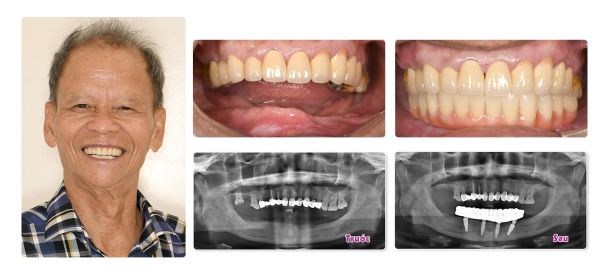

Như trường hợp của chú Dũng (65 tuổi), lựa chọn đeo hàm tháo lắp trong suốt 2 năm với hy vọng khôi phục chức năng ăn nhai. Trái với mong đợi, 2 năm qua chú Dũng vừa không thể ăn uống thoải mái, phải thường xuyên ăn cháo, vừa nói chuyện không liền mạch và phát âm không chuẩn xác. May mắn đến Nha khoa Elite Dental gặp Tiến sĩ Bác sĩ Trần Hùng Lâm, chú được chẩn đoán, đánh giá và chỉ định cấy 4 trụ Implant vào hàm dưới để phục hồi răng mất theo kỹ thuật ProArch/All-on-4. Kết thúc quá trình điều trị, chú Dũng đã sở hữu hàm răng khỏe đẹp như ý, hoàn toàn tìm lại được cảm giác ăn nhai thoải mái và tự tin trò chuyện với người thân, bạn bè.

Sau đây là những hình ảnh ghi nhận kết quả phục hình thành công sau khi trồng răng Implant của khách hàng tại Elite Dental: